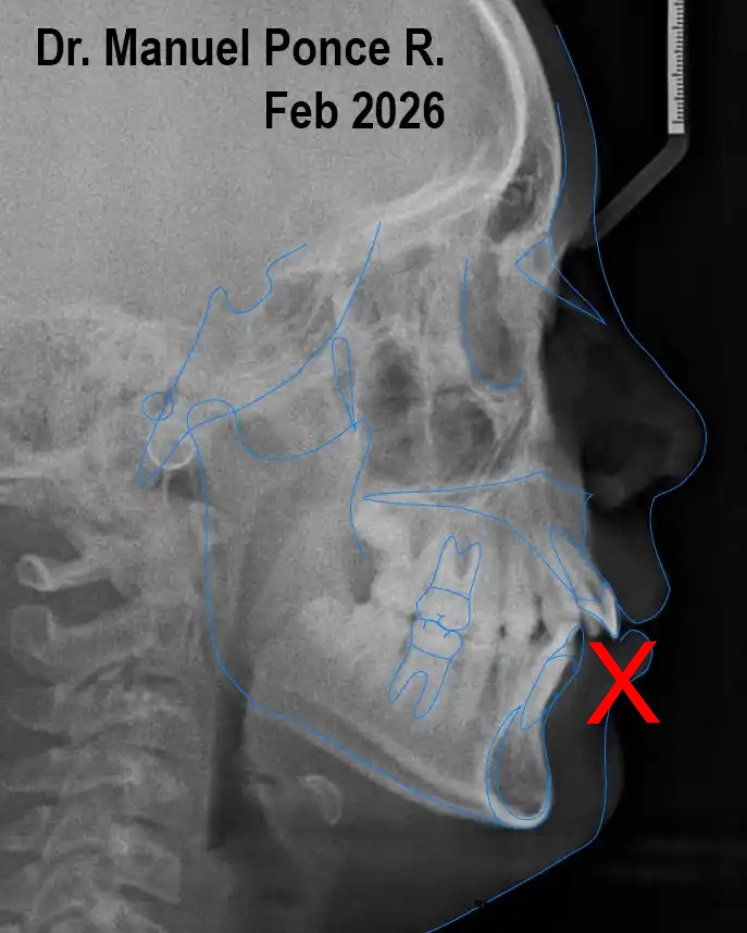

La observación clínica, junto con el estudio de modelos, fotografías y cefalometría, permitió analizar la posición dentaria, la relación esqueletal y el espacio disponible. Esto permitió definir que era oportuno intervenir en esta etapa.

Se indicó ortodoncia interceptiva con expansión palatina para mejorar el desarrollo transversal del maxilar, optimizar el espacio disponible y acompañar el crecimiento en un momento favorable.

Se indicó un expansor palatino como parte de una fase interceptiva temprana, orientada a mejorar la dimensión transversal del maxilar, optimizar el espacio disponible y acompañar el crecimiento de manera más predecible.